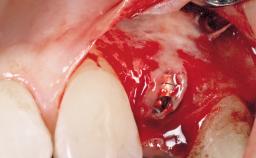

Early (Type 2) placement in a healthy, non-smoking male patient aged 28 years who required removal and replacement of the maxillary right central incisor due to external root resorption. A horizontal bone deficit requires a simultaneous augmentation procedure. The overall esthetic risk is high due to the horizontal bone deficit, medium to high lip line with exposure of the soft tissue margin when smiling, and the patient’s high esthetic expectations.

After flapless tooth extraction and a healing period of 6 weeks, a standard-diameter one-piece implant is placed. A gap between the implant and the facial bone wall is filled with autogenous bone chips harvested from the anterior nasal spine and covered with DBBM particles. Contour augmentation on the facial aspect is achieved using DBBM particles and a collagen membrane, according to the principles of guided bone regeneration (GBR). The flap is coronally repositioned for semisubmerged healing.